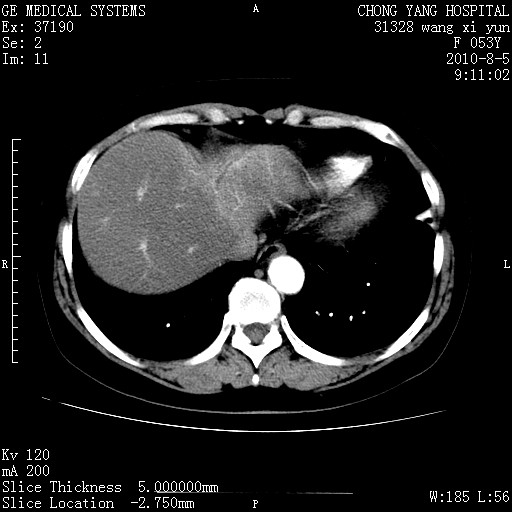

标题: CT28214:F41Y 血尿二十天,建议盆腔平扫加增强。

1)考虑肝左叶胆管细胞癌。2)脂肪肝。

支持胆管细胞ca。